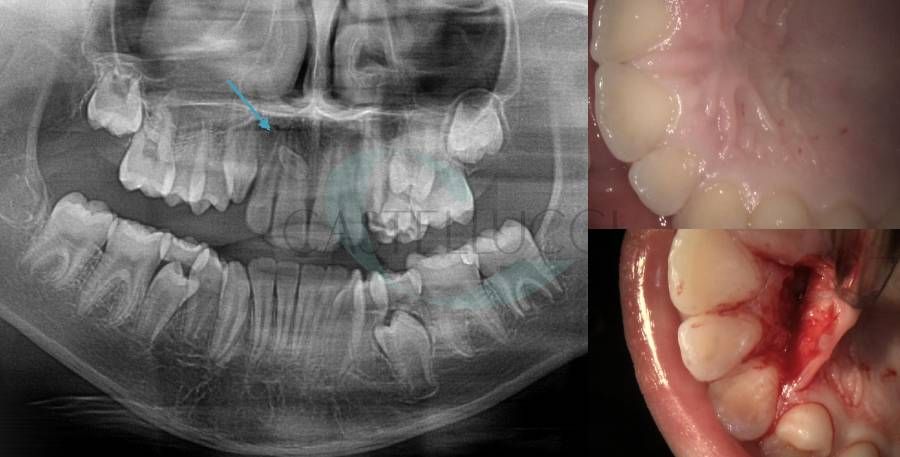

• Terapia chirurgica degli elementi dentari decidui con ritardo di permuta

• Disinclusione chirurgica degli elementi dentari permanenti ritenuti